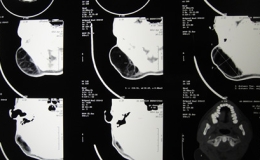

目前我科在刘宏科主任带领下,全面开展微创技术,其中腹腔镜阑尾切除术(LA)是随着腹腔镜技术发展而兴起的一种新的手术方法。1983年Semm报道了首例经腹腔镜切除非急性炎症的阑尾,较腹腔镜胆囊切除术早4年,而腹腔镜下急性阑尾炎的阑尾切除术是1987年Semm首次报道的。大量前瞻性、随机对照的研究证实,腹腔镜阑尾切除术与传统开腹阑尾炎切除术(CA)比较,其优越性是住院时间短,术后并发症少,恢复快。对手术前不能确诊的病例,术中探查较开腹手术视野宽阔,对腹膜后、肝下异位阑尾寻找和切除更显其优越性,肥胖病人更适合,是一种安全、可靠的微创手术方法。

一般采取全麻下手术,一般采取三孔法,脐部,脐部与耻骨联合中点偏左侧,反麦氏点,分别建立1CM,0.5CM,1CM操作孔,系膜采用血管夹夹闭,根部条件较好者采用血管夹夹闭,水肿者采用7号丝线结扎的办法,整个手术视野清晰,探查方便,最大限度减少腹腔干扰,有利于患者术后恢复,平均3天即可出院。